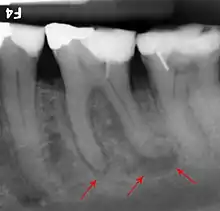

If disease is identified through this process, then a full periodontal analysis is performed, often by dental hygienists, oral health therapists, or specialist periodontists. This involves full mouth periodontal probing and taking measurements of pocket depths, clinical attachment loss and recession. Along with this other relevant parameters such as plaque, bleeding, furcation involvement and mobility are measured to gain an overall understanding of the level of disease. Radiographs may also be performed to assess alveolar bone levels and levels of destruction.[40]

Periodontal disease encompasses a number of diseases of the periodontal tissues that result in attachment loss and destruction of alveolar bone.[11]

An individual's host response plays an important role in the pathogenesis of periodontal disease. Even in a mouth where the gingiva appear healthy, there is constant low-level inflammatory response facilitated by the host to manage the constant bacterial load of plaque micro-organisms. Leukocytes and neutrophils are the main cells that phagocytose bacteria found in the gingival crevice or pocket. They migrate from the tissues in a specialized exudate called gingival crevicular fluid also known as GCF. Neutrophils are recruited to the gingival crevice area as they are signalled to by molecules released by plaque microorganisms. Damage to epithelial cells releases cytokines which attract leukocytes to assist with the inflammatory response. The balance between normal cell responses and the beginning of gingival disease is when there is too much plaque bacteria for the neutrophils to phagocytose and they degranulate, releasing toxic enzymes that cause tissue damage. This appears in the mouth as red, swollen and inflamed gingiva which may bleed when probed clinically or during tooth brushing. These changes are due to increased capillary permeability and an influx of inflammatory cells into the gingival tissues. When gingival disease remains established and the aetiology is not removed, there is further recruitment of cells such as macrophages, which assist with the phagocytic digestion of bacteria, and lymphocytes, which begin to initiate an immune response.[22] Pro-inflammatory cytokines are produced inside the gingival tissues and further escalate inflammation, which impacts the progression of chronic systemic inflammation and disease. The result is collagen breakdown, infiltrate accumulation as well as collagen breakdown in the periodontal ligament and alveolar bone resorption. At this stage, the disease has progressed from gingivitis to periodontitis and the loss of supporting periodontium structure is irreversible.[21]